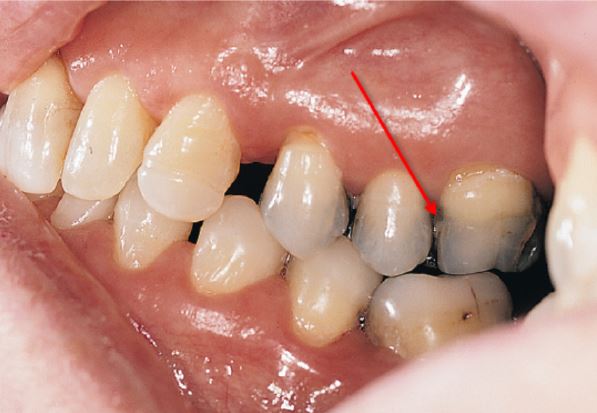

What is most likely shown in the image, as indicated by the red arrow?

Exogenous stains as an effect of dental amalgam

Formation of Nasmyth's membrane over the enamel

Tooth discoloration caused by excessive fluoride exposure during tooth development

Tooth discoloration caused by tetracycline consumption during tooth development